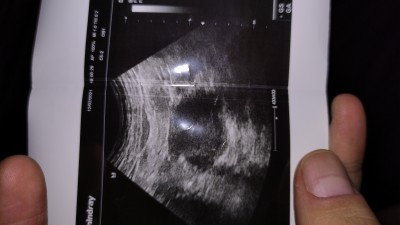

Kızlar 5+1 deyim bugun doktora gittim ve keseyi tam net gormek için 3 gün sonra çağırdı. Kesenin olduğu yeri işaretledi ama o kesenin yanında oluşan bir kese daha olabilir dedi çok ufak bir şey gözüküyordu ultrason da böyle bir durum yaşayan ikiz anneleri var mı ?

Gebelik haftası 5+1